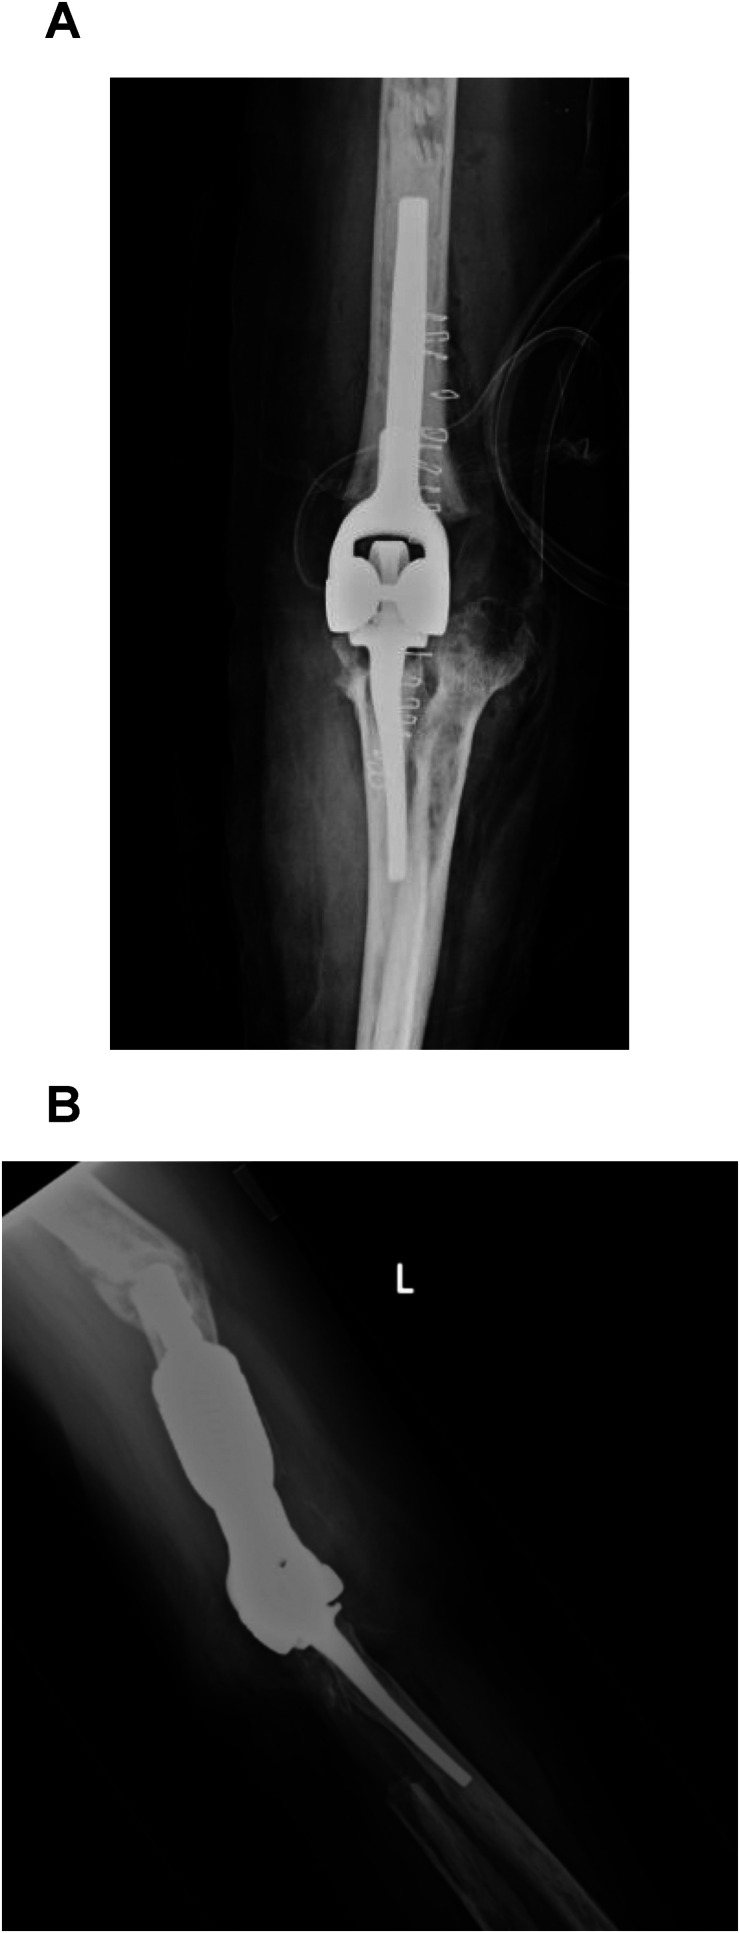

As the number of total elbow arthroplasty (TEA) continues to increase worldwide, one might predict the number of revision TEA would rise as well. The most common indications for revision TEA include (a) loosening, (b) infection, and (c) periprosthetic fracture. Although the rate of revision TEA procedures continues to rise due to the infrequency in which they are performed compared to other arthroplasty surgeries, no gold standard algorithm or procedure for managing severe ulnar bone loss in revision TEA has been determined. Various surgical techniques and strategies including allograft-prosthesis composite, custom long prosthesis with or without allograft, and resection arthroplasty have all been employed in attempting to address severe ulnar bone loss in revision TEA. Though the reported outcomes are mixed at best between each treatment strategy with similar complication rates. Another option is implanting the ulnar component into the radius. In those patients with severe ulnar bone loss, a humeroradial TEA revision can provide stability, restore range of motion, and provide pain relief.

Abstract Image